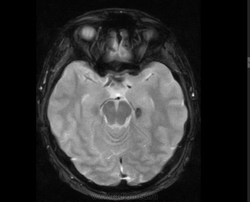

М, 27 лет. Жалобы на головные боли. ЧМТ в анамнезе. Стационар выставил внутримозговую гематому по КТ, полечили, отпустили.  К нам пришел на контроль.

Локализация таламус, граница коркового/мозгового, похоже на множественные кавернозные ангиомы. То, что в левой лобной?

Хочу посоветоваться с коллегами).  Дифференциальный ряд построить. Например токсоплазмоз, метастазы....в общем жду.

Сложно представить у молодого человека и каверномы, и метастазы одновременно.

Наверное, все же множественные каверномы, слева -осложненная кровоизлиянием.

Пришел к выводу, что сдесь все таки не каврномы, а мелкоочаговые кровоизлияния (ДАП). Учитывая травму и пребывание после этого  пациента в коме.